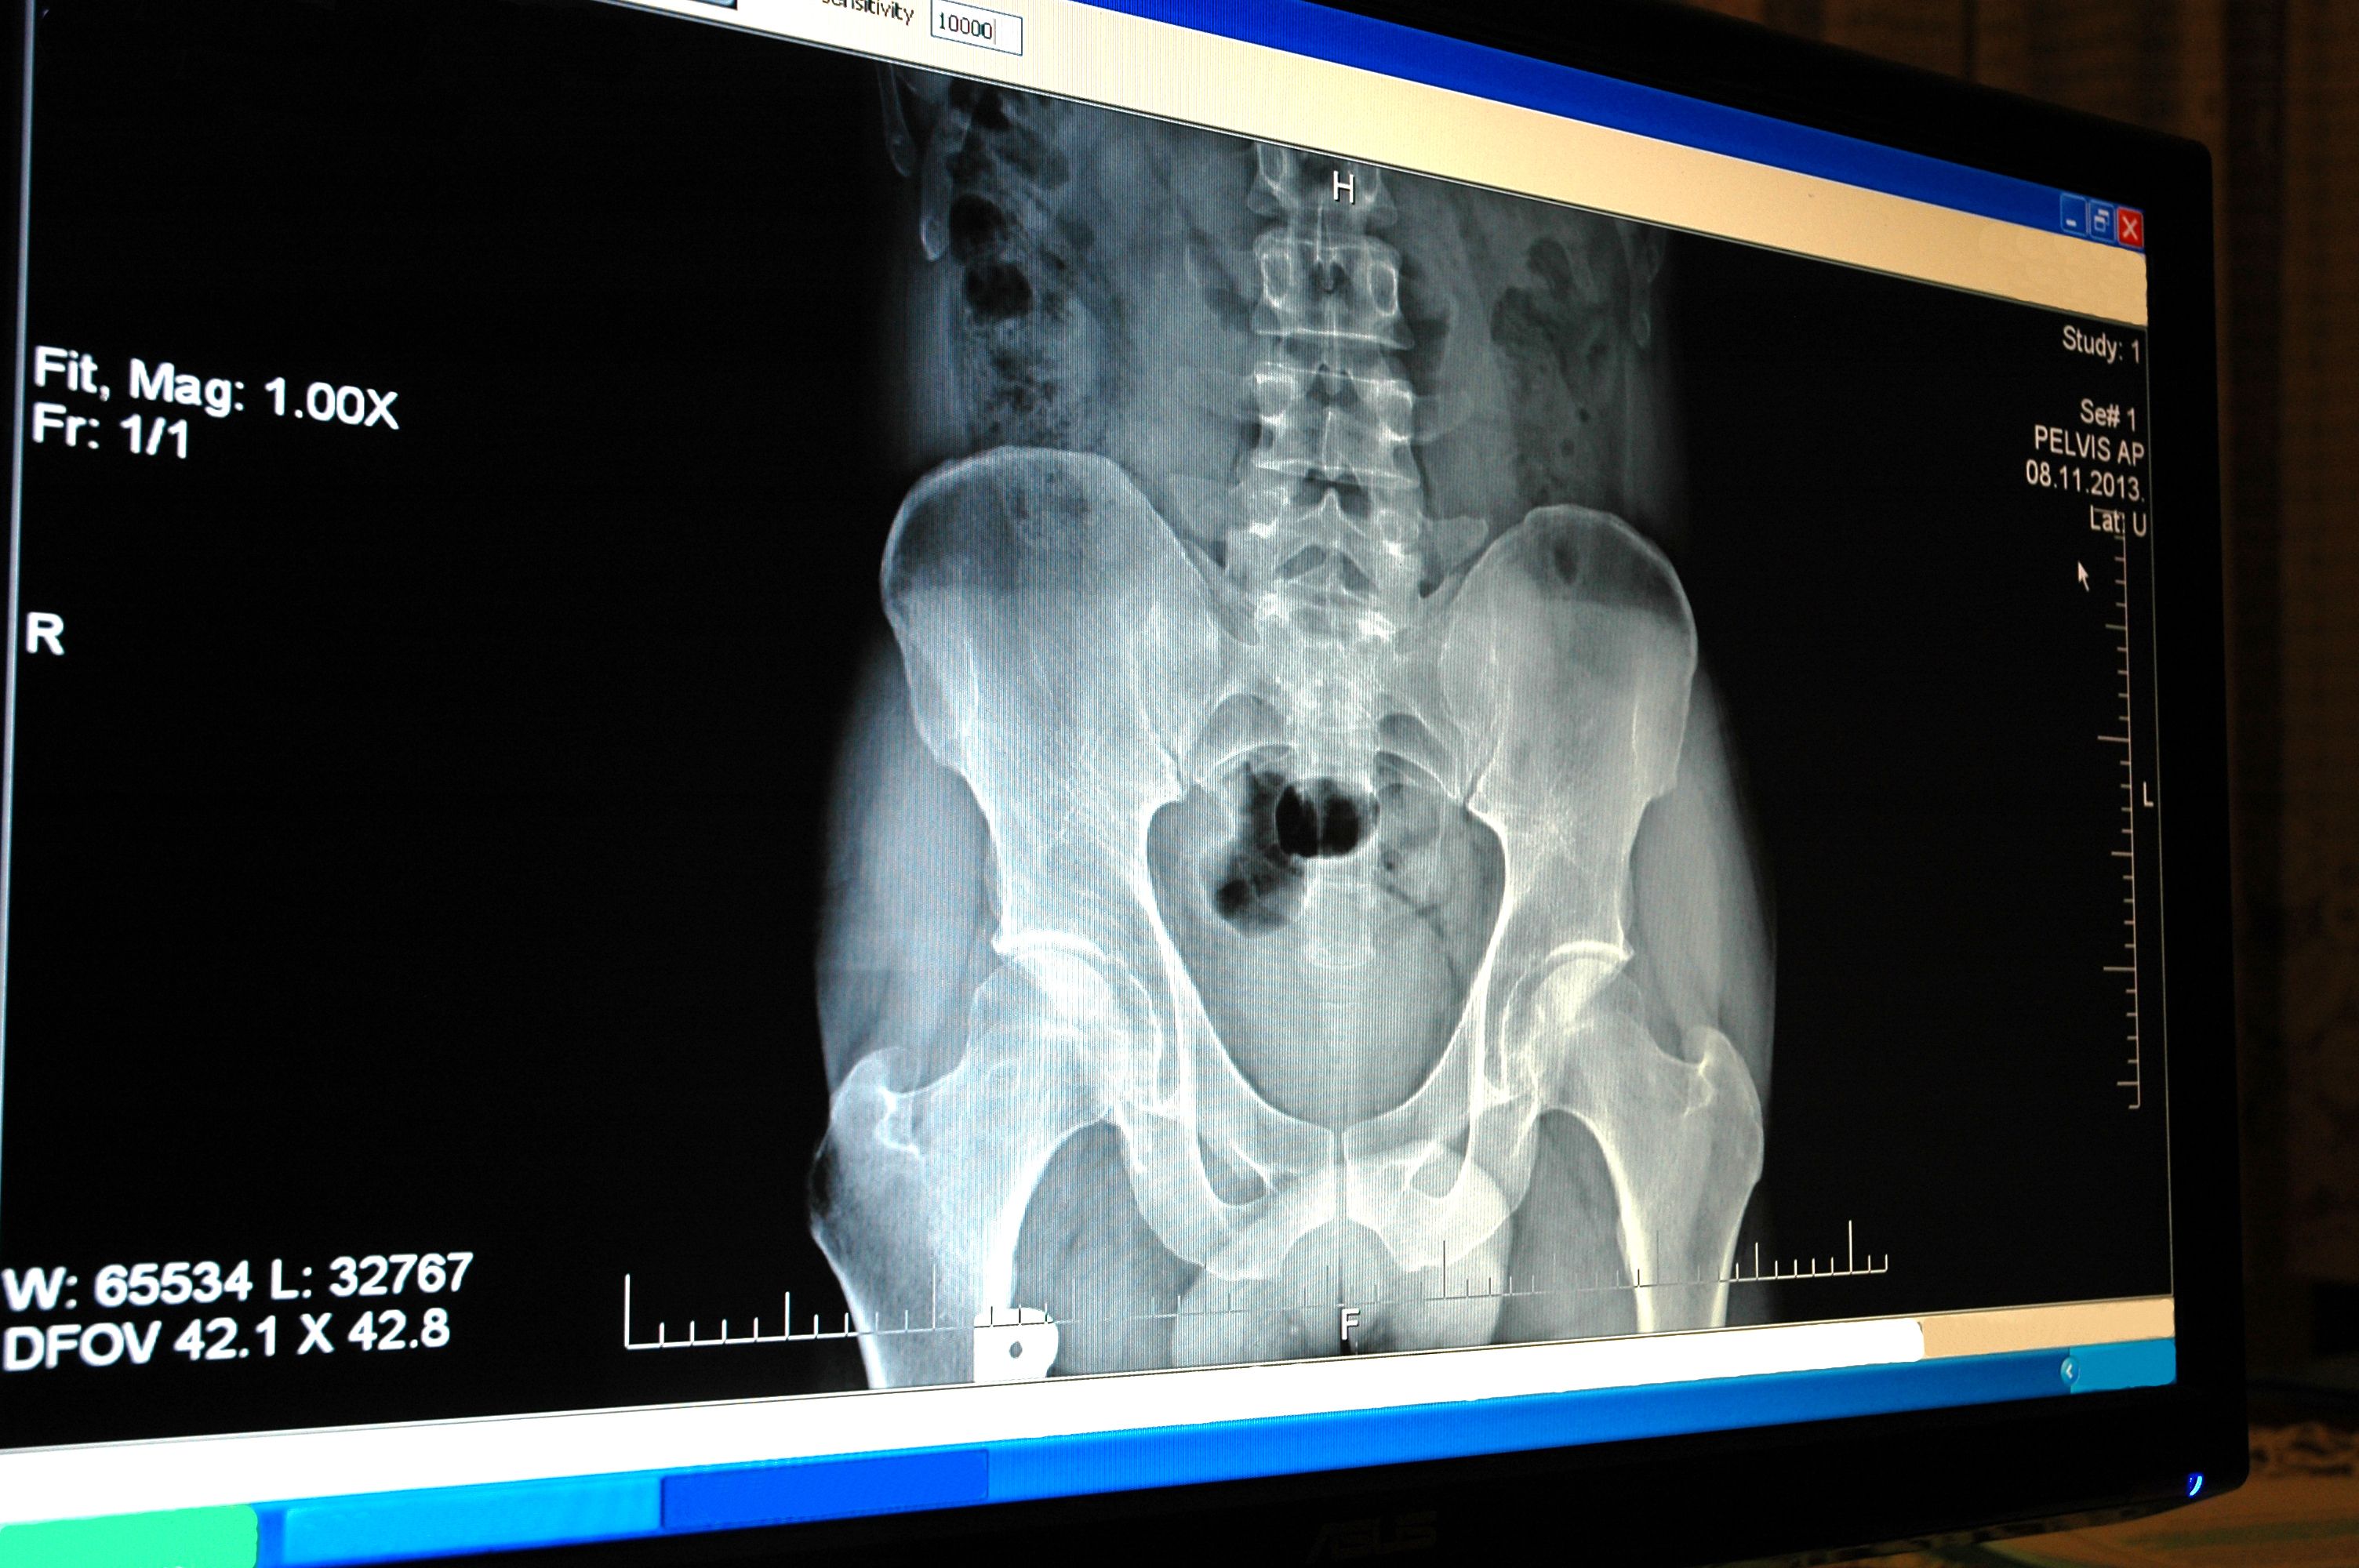

အမျိုးသမီးများ သည် သွေးဆုံးပြီး၌ အရိုးပွရောဂါဖြစ်နိုင်ချေ မြင့်သည်။ အရိုး ပွရောဂါနှင့် ဆက်စပ်သော အရိုးကျိုးမှုများသည် အများအား ဖြင့် တင်ပဆုံ၊ လက်ကောက်ဝတ်နှင့် ကျောရိုးတွင် ဖြစ်ပွား သည်။ သို့သော် မည်သည့်အရိုးမဆို ထိခိုက်နိုင်ပါသည်။ အချို့ ကျိုးသွားသော အရိုးများသည် ပြန်လည်မကောင်းမွန် လာတော့ပါ။ အထူးသဖြင့် တင်ပါးဆုံရိုးကျိုးပါက ဆိုးဝါးသည်။

ရောဂါ အစောပိုင်းတွင် လက္ခဏာများ မပေါ်ပါ။ အချိန် ကြာပါက ကျောနာခြင်း၊ လည်ပင်းနာခြင်း၊ ကိုယ်နေကိုယ် ထား ကုန်းခြင်း၊ အရပ် တဖြည်းဖြည်း နိမ့်လာခြင်းတို့ ဖြစ်နိုင် သည်။ အချို့တွင် ပထမဆုံး လက္ခဏာသည် အရိုးကျိုးခြင်း (နံရိုး၊ လက်ကောက်ဝတ် နှင့် တင်ပါးဆုံ) ဖြစ်သည်။ ကျောရိုး သည် ပြားကာ ကျိုးနိုင်ပြီး ၎င်းသည် အဖြစ်အများဆုံးဖြစ် သည်။ တင်ပါးဆုံရိုးကျိုးခြင်းသည် မသန်စွမ်းမှုကို အဆိုးဆုံး ဖြစ်စေသည်။

အရိုး သတ္ထုသိပ်သည်းဆ စစ်ဆေးမှုသည် အရိုးကျန်းမာ ရေးကို စစ်ဆေးရန် အကောင်းဆုံးနည်းလမ်း ဖြစ်ပါသည်။ ဤ စစ်ဆေးမှုသည် မနာကျင်ပါ။ ကုတင်ပေါ်တွင် လဲလျောင်းကာ scanner မှ ခန္ဓါကိုယ်အပေါ် ဖြတ်သွားပါသည်။ ဖြစ်ပွားမှု အများစုတွင် အရိုးအနည်းငယ်ကိုသာ စစ်ဆေးပါသည်။ အများအားဖြင့် တင်ပဆုံ၊ လက်ကောက်ဝတ်နှင့် ကျောရိုးတို့ ဖြစ်ပါသည်။